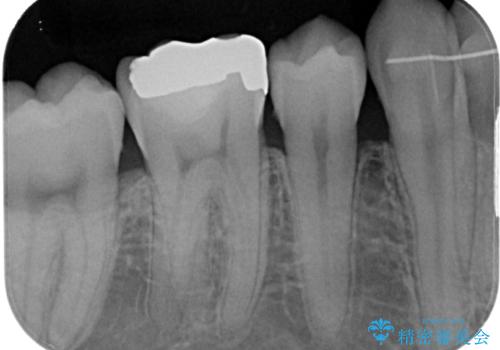

- 銀歯をセラミックにしたいとのことで来院された患者様です。検査の結果、メタルインレーが大きくご自身の歯の残る量を考慮して、オールセラミッククラウンによる補綴治療を行っていくことにしました。

拡大鏡視野下で、メタルインレー、虫歯の除去を行いオールセラミッククラウンに適した形に整えました。

違和感もなく、適合性も良い被せものを入れることができました。

適合の高い被せものを入れることにより再び虫歯になるリスクを下げることができます。